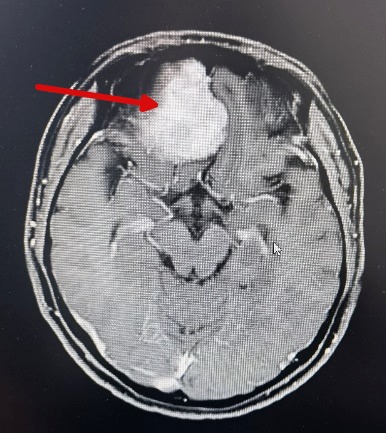

【医讯速览·新闻】第33期:又一首例!我院神经外科完成1例颅底肿瘤手术